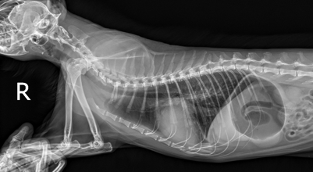

이번에 소개해드릴 환자는 10살의 중성화된 암컷 코리안숏헤어로, 최근 호흡수가 눈에 띄게 증가하고 양쪽 뒷다리를 갑자기 사용하지 못하는 증상이 발생하여 본원에 내원하였습니다. 해당 증상은 단순한 호흡기 문제나 신경 질환뿐 아니라 심장 질환과 혈전 합병증 가능성까지 함께 고려해야 하는 상황이었기 때문에, 정확한 원인 평가를 위해 방사선 검사와 심장 초음파 검사를 진행하였습니다.

방사선 검사에서 다음과 같은 소견이 확인되었습니다.

환자의 방사선검사 사진/ 출처: 24시 동탄리더스동물의료원

- 심장 실루엣이 valentine shape로 관찰되었으며, 실제 측정 결과 심장 크기 VHS 9.7v, VD short axis 5.3v로 심한 심비대가 확인되었습니다.

- 폐의 앞쪽을 따라 주행하는 폐정맥이 미약한 확장된 모습을 보였습니다.

- 양쪽 폐의 후엽에서 폐 실질 하얗게 보이는 소견(alveolar pattern)이 관찰되었습니다.

- 우측 폐 중엽과 후엽 사이 미약한 fissure line( 얇은 선 모양의 변화) 관찰되었습니다.

- 또한 식도와 위 안에 가스가 다량 차 있는 모습이 확인되었습니다.

위 소견을 종합하였을 때, 심한 심비대와 폐수종 소견이 확인되어 고양이 비대성 심근병증(HCM), 제한성 심근병증(RCM) 등을 포함한 심근병증(cardiomyopathy)가 강하게 의심되었습니다.